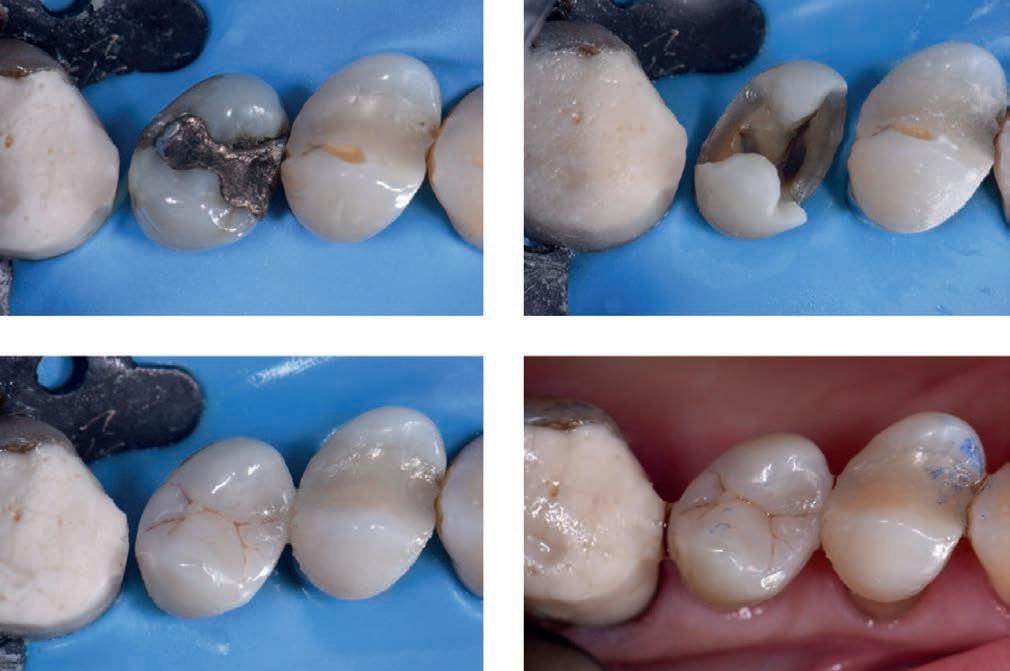

A stable ASA 2 65-year old female presented to the practice for restorative dentistry with a medical history significant for a non-descript immunoglobulin deficiency, for which she receives regular infusions. She reports no known drug allergies. Clinically, she was diagnosed with an occlusal peripheral rim fracture leaving a food trap on tooth 1.4 (FDI notation). Tooth 15 featured an extensive amalgam with extreme proximity to the distal marginal ridge, which exhibited distal vertical axial fractures as a result of cyclic expansion-contraction over time.

The restorative goal of minimally invasive direct dentistry would be complicated by the undoubtedly dark dentin substrate under the amalgam. A material was sought that featured both an excellent chameleon mechanism as well as physical properties to maximize the prognosis of direct restorations in this area.

Restorative procedure

The patient was subjected to topical anesthetic prior to buccal infiltration using 1 carpule of 2% Lignocaine with 1:100,000 epinephrine. A rubber dam was affixed prior to preparation of tooth 15MO with dissection of the distal vertical marginal ridge fracture. The margins of tooth 14O and 15MOD were refined before bevelling as the ends of enamel rods facilitate better bonding relative to the sides of enamel rods. A 27 micron aluminum oxide micro air abrasion treatment was completed prior to affixing, wedge and matrix to reconstruct the mesial marginal ridge of tooth 15. A matrix-inmatrix solution was used to recreate the proximoaxial contour of 15D This provided hermetic closure at the proximogingival cavosurface margin as well as an ideal contour for the missing axial wall.

Following a total etch technique, a 2% Chlorhexidine scrub was completed for 30 seconds and the dentin blot dried to a moist state. A 5th generation bond was applied, air thinned and cured as per manufacturer instructions. Microlayers are important during the delicate first 5 minutes of hybrid layer formation, and were completed using 0.25mm increments of CLEARFIL MAJESTY™ Flow (Kuraray Noritake Dental Inc.). This technique can be expected to increase significantly the shear bond strength to dentin1,2 This was completed both in the proximal box floor area as well as mid-occlusally. The marginal ridge was completed using CLEARFIL MAJESTY™ ES-2 Universal (Kuraray Noritake Dental Inc.). Since the dentin base was heavily stained, CLEARFIL MAJESTY™ Flow was used before utilizing CLEARFIL MAJESTY™ ES-2 Universal in a lobe-by-lobe creation of occlusal anatomy. Post-operative occlusal checks verify that the restoration is conformative to occlusion and esthetically excellent with no visible marginal show.

Premolar case with Clearfil Majesty™ ES-2 Universal

Figure 1: Initial situation: insufficient composite restoration in tooth 36 Figure 2: The cavity after preparation Figure 3: Final result: a natural-looking aesthetic restoration